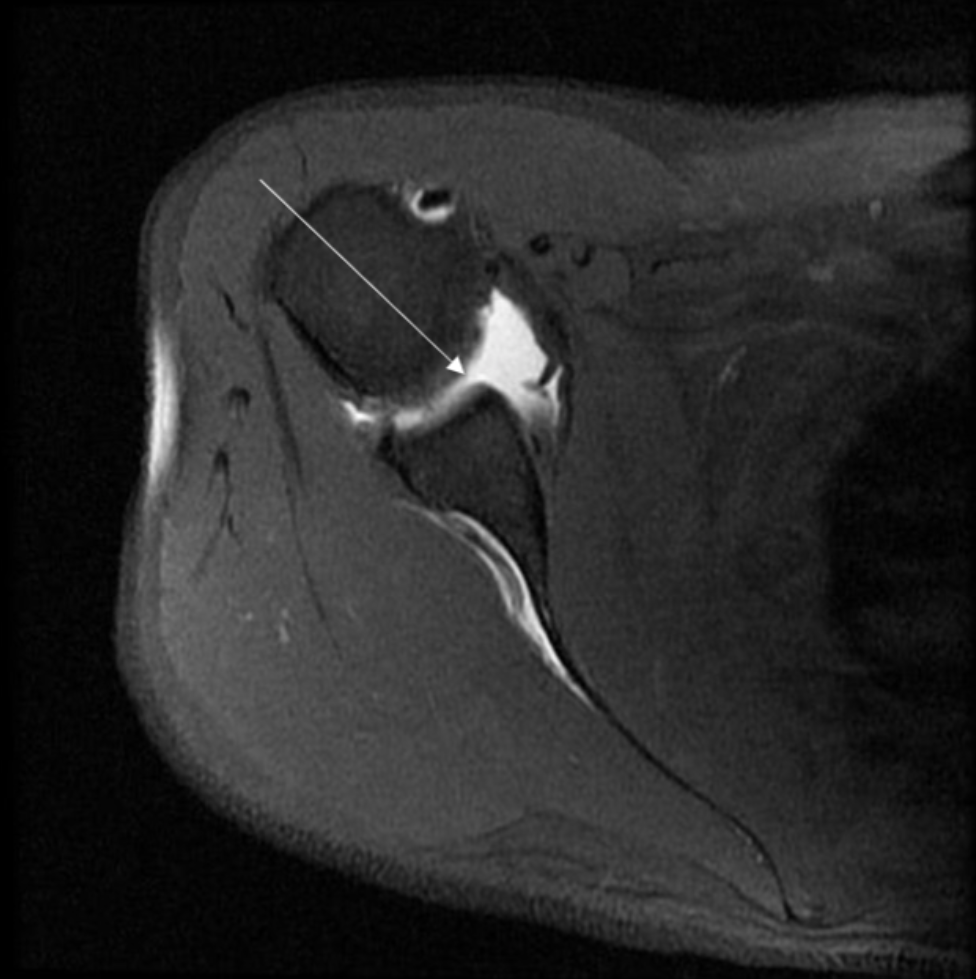

Describe the pathology indicated by the arrow (Ax T1 FS - arthrogram).

SLAP tear